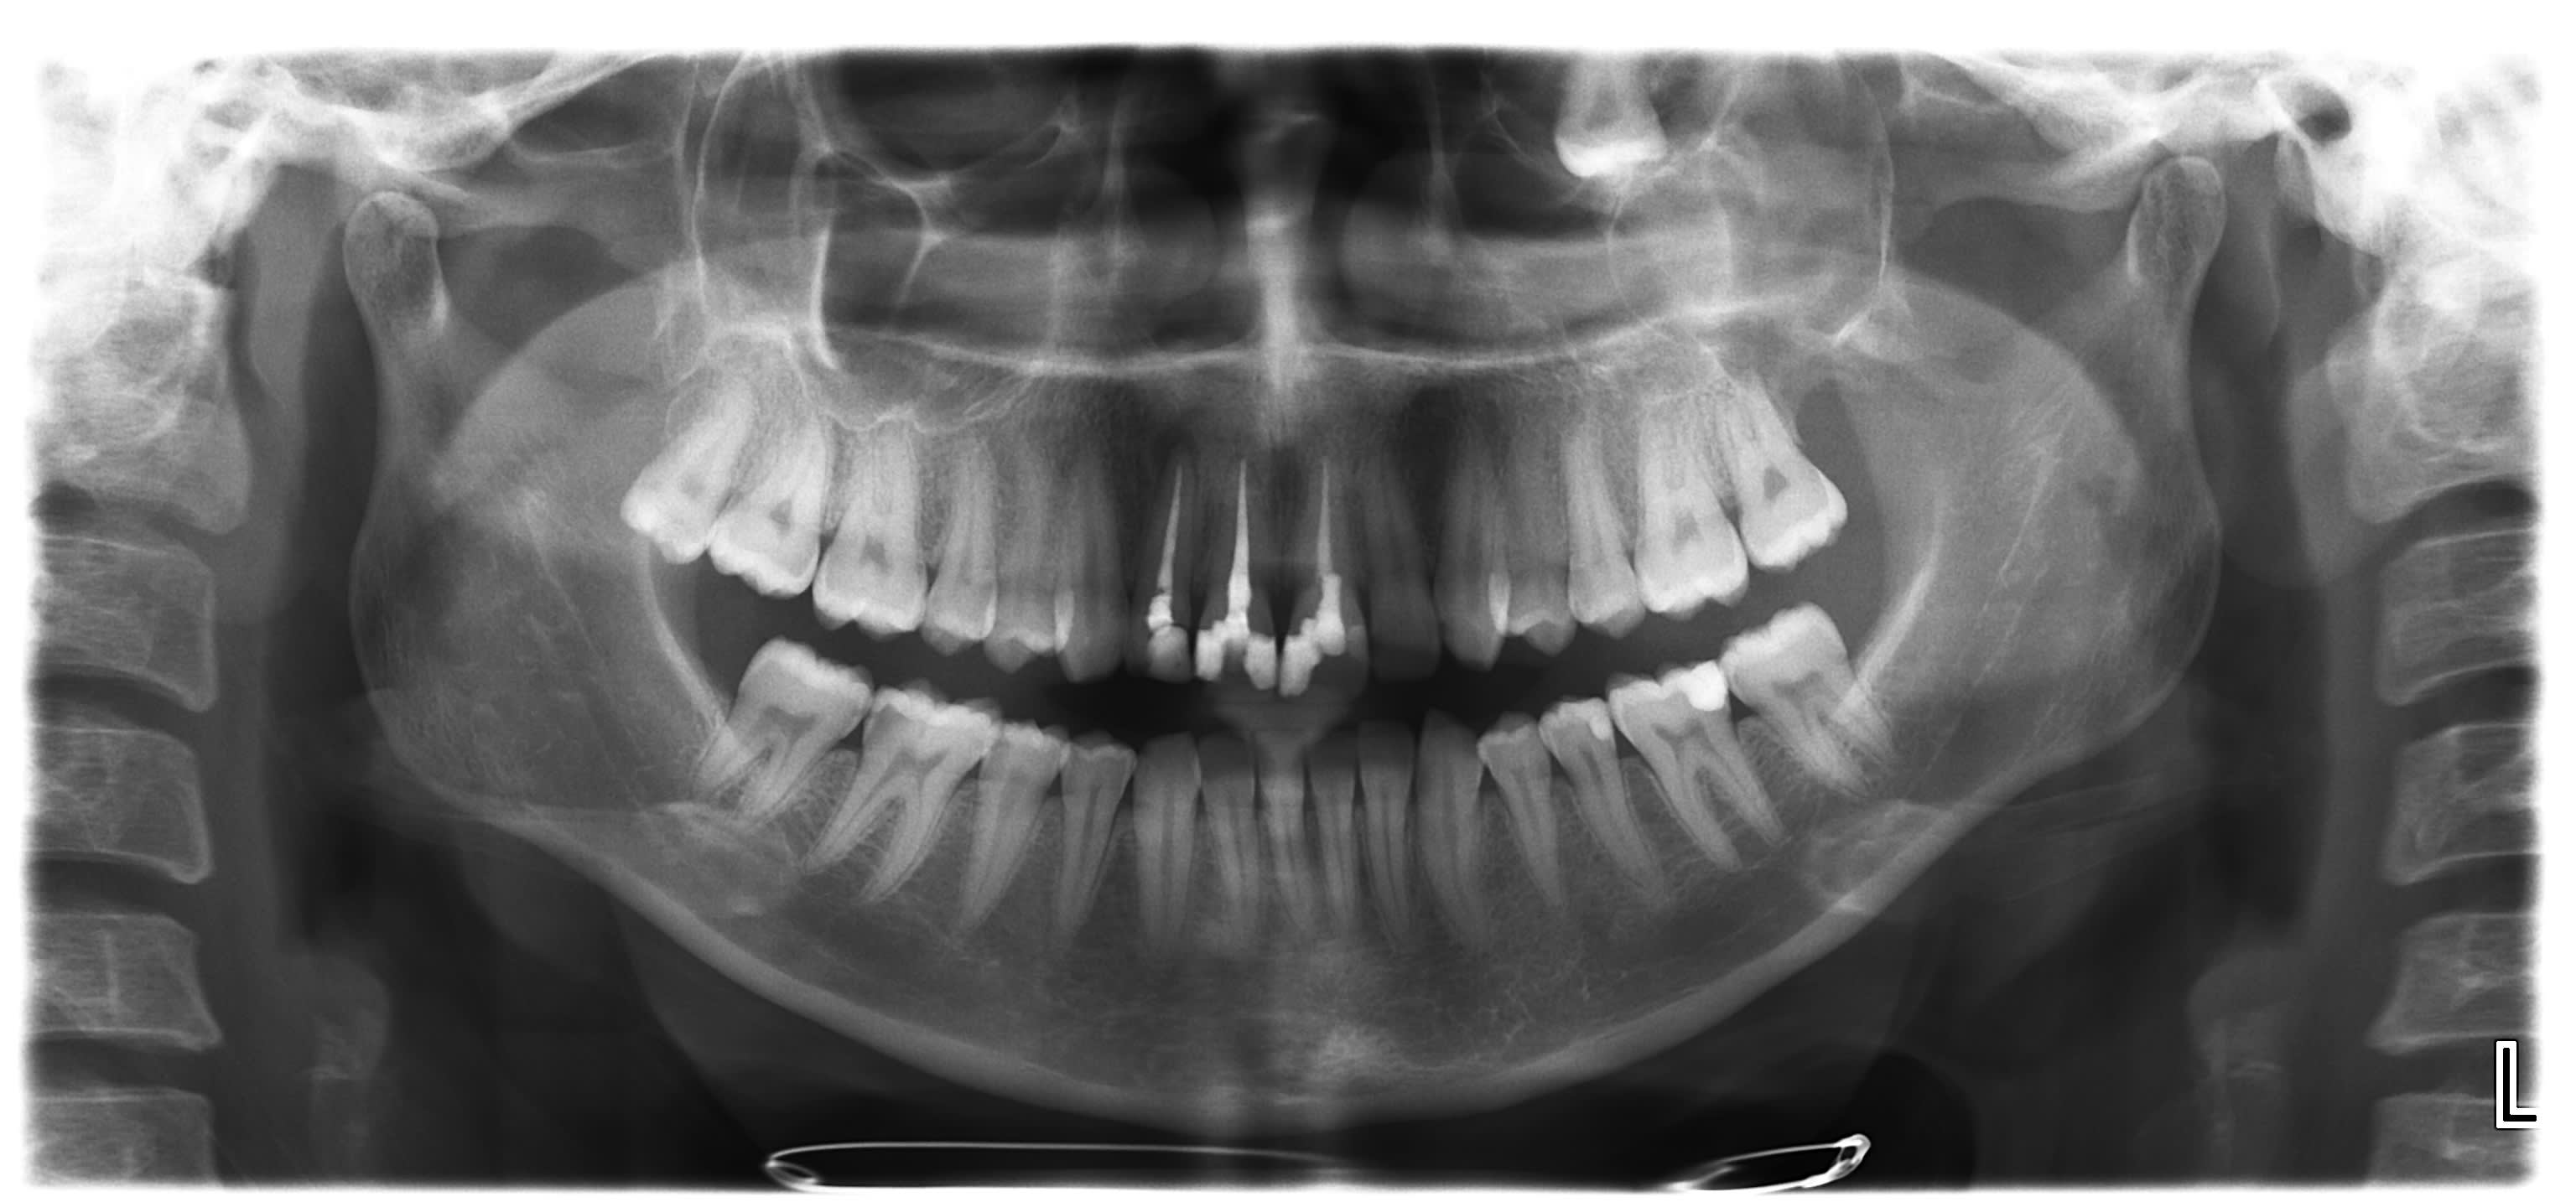

Juste pour info le CBCT qui demontre bien qu une PANO est une somme de projection, rotation etc...

Sur la coupe frontale on voit que la dent est au niveau du cornet inferieur de la paroi nasale et non derriere la cavite orbitaire :0)